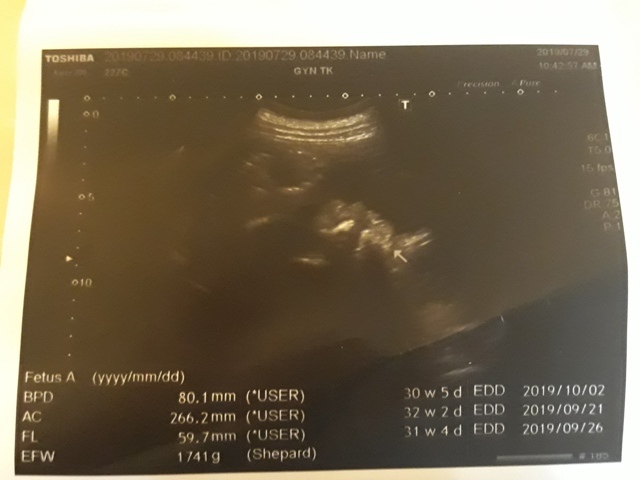

| 仙人掌(2019/07/29)的真心話 星期一 天氣晴 編號19-199 |

近八次產檢資料統計↓

| 2019年07月29日 | 80.1mm (8%) | 266.2mm (10%) | 59.7mm (10%) | 1741g (32%) | 136 |

| BPD:胎兒頭骨橫徑 AC:胎兒腹圍的長度 FL:胎兒大腿骨的長度 EFW:胎兒的體重 括弧內百分比為較上次產檢的成長比例 | |||||